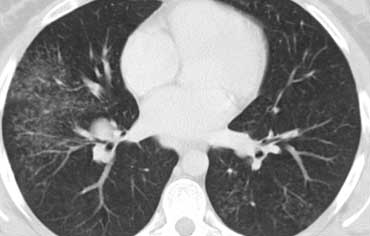

Sarcoidosis: hình ảnh điển hình với các nốt dọc theo bó mạch phế quản và các khe liên thùy. Lưu ý hạch vôi hóa một phần ở rốn phổi trái.

Dấu hiệu HRCT trong Sarcoidosis

- Dấu hiệu thường gặp:

- Các nốt nhỏ phân bố theo đường bạch huyết (dọc theo bề mặt dưới màng phổi và các khe liên thùy, dọc theo vách liên tiểu thùy và bó mạch phế quản).

- Ưu thế ở vùng trên và giữa phổi.

- Hạch to ở rốn phổi trái, rốn phổi phải và cạnh khí quản (dấu hiệu 1-2-3). Thường kèm vôi hóa.

Hình ảnh điển hình của sarcoidosis với hạch to rốn phổi và các nốt nhỏ dọc theo bó mạch phế quản (mũi tên vàng) và dọc theo các khe liên thùy (mũi tên đỏ).

Hình ảnh chi tiết với biểu hiện HRCT điển hình gồm các nốt dọc theo bó mạch phế quản (mũi tên đỏ) và các khe liên thùy (mũi tên vàng).

Đây là phân bố theo đường bạch huyết điển hình của các nốt.

Bên trái là một hình ảnh điển hình khác của sarcoidosis với hạch to trung thất và các nốt nhỏ phân bố theo đường bạch huyết dọc theo bó mạch phế quản và dọc theo các khe liên thùy (mũi tên vàng).

Luôn tìm kiếm các nốt nhỏ dọc theo các khe liên thùy, vì đây là dấu hiệu rất đặc hiệu và điển hình của sarcoidosis.